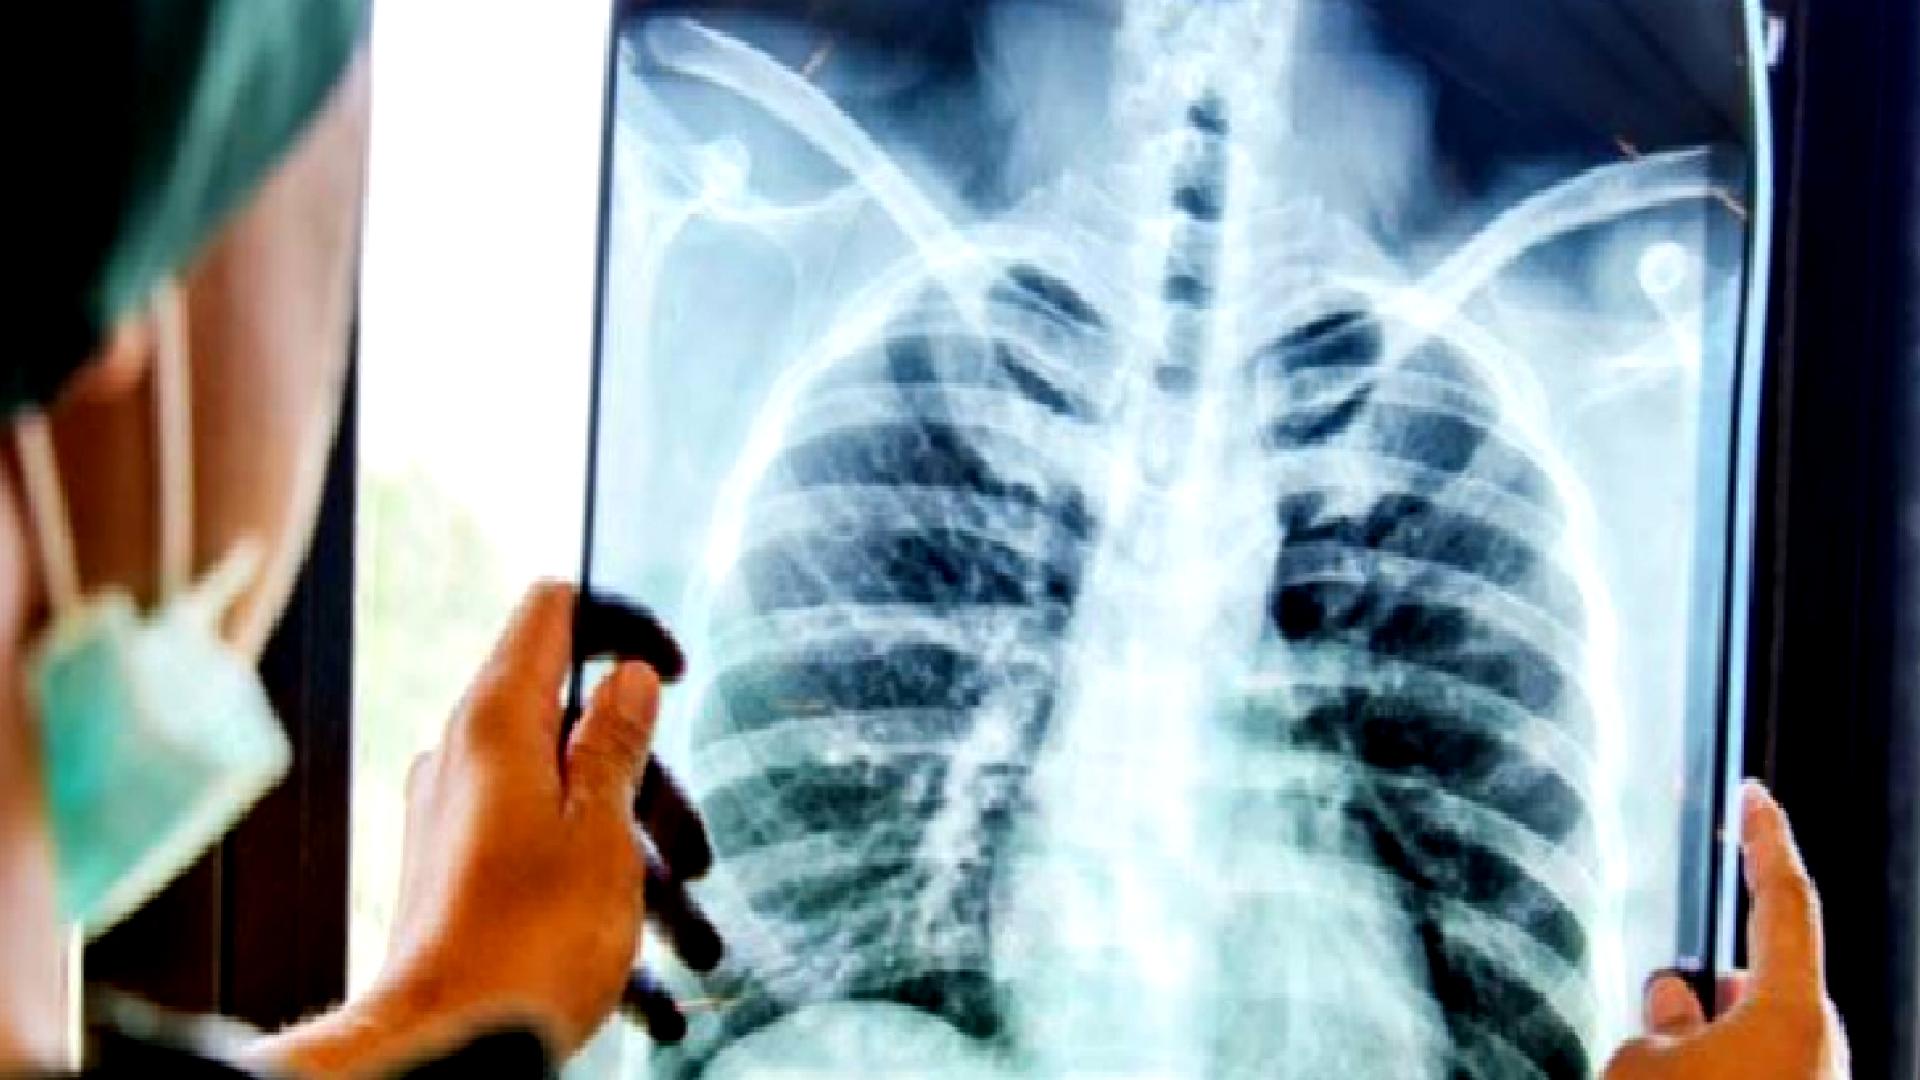

Zatürre, akciğerlerde hava keseciklerinin iltihaplanması sonucu oluşan bir enfeksiyondur. Bakteri, virüs veya mantarlar nedeniyle gelişebilir. Özellikle çocuklar, yaşlılar ve bağışıklığı zayıf bireyler için ciddi olabilir.